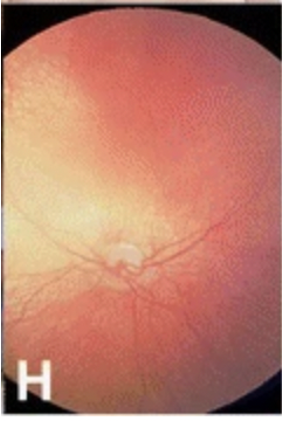

Bilateral cataracts are seen in 75% of patients with Vici syndrome making it one of the classical diagnostic features.[3] Other ocular features include optic nerve hypoplasia, visual impairment, nystagmus, and fundus hypopigmentation.[7] In some individuals, there is evidence of optic pathway misrouting on visual evoked potential testing. Optical coherence tomography shows a poorly defined and lesser depressed fovea, similar to that of individuals with typical albinism.[3] [7]